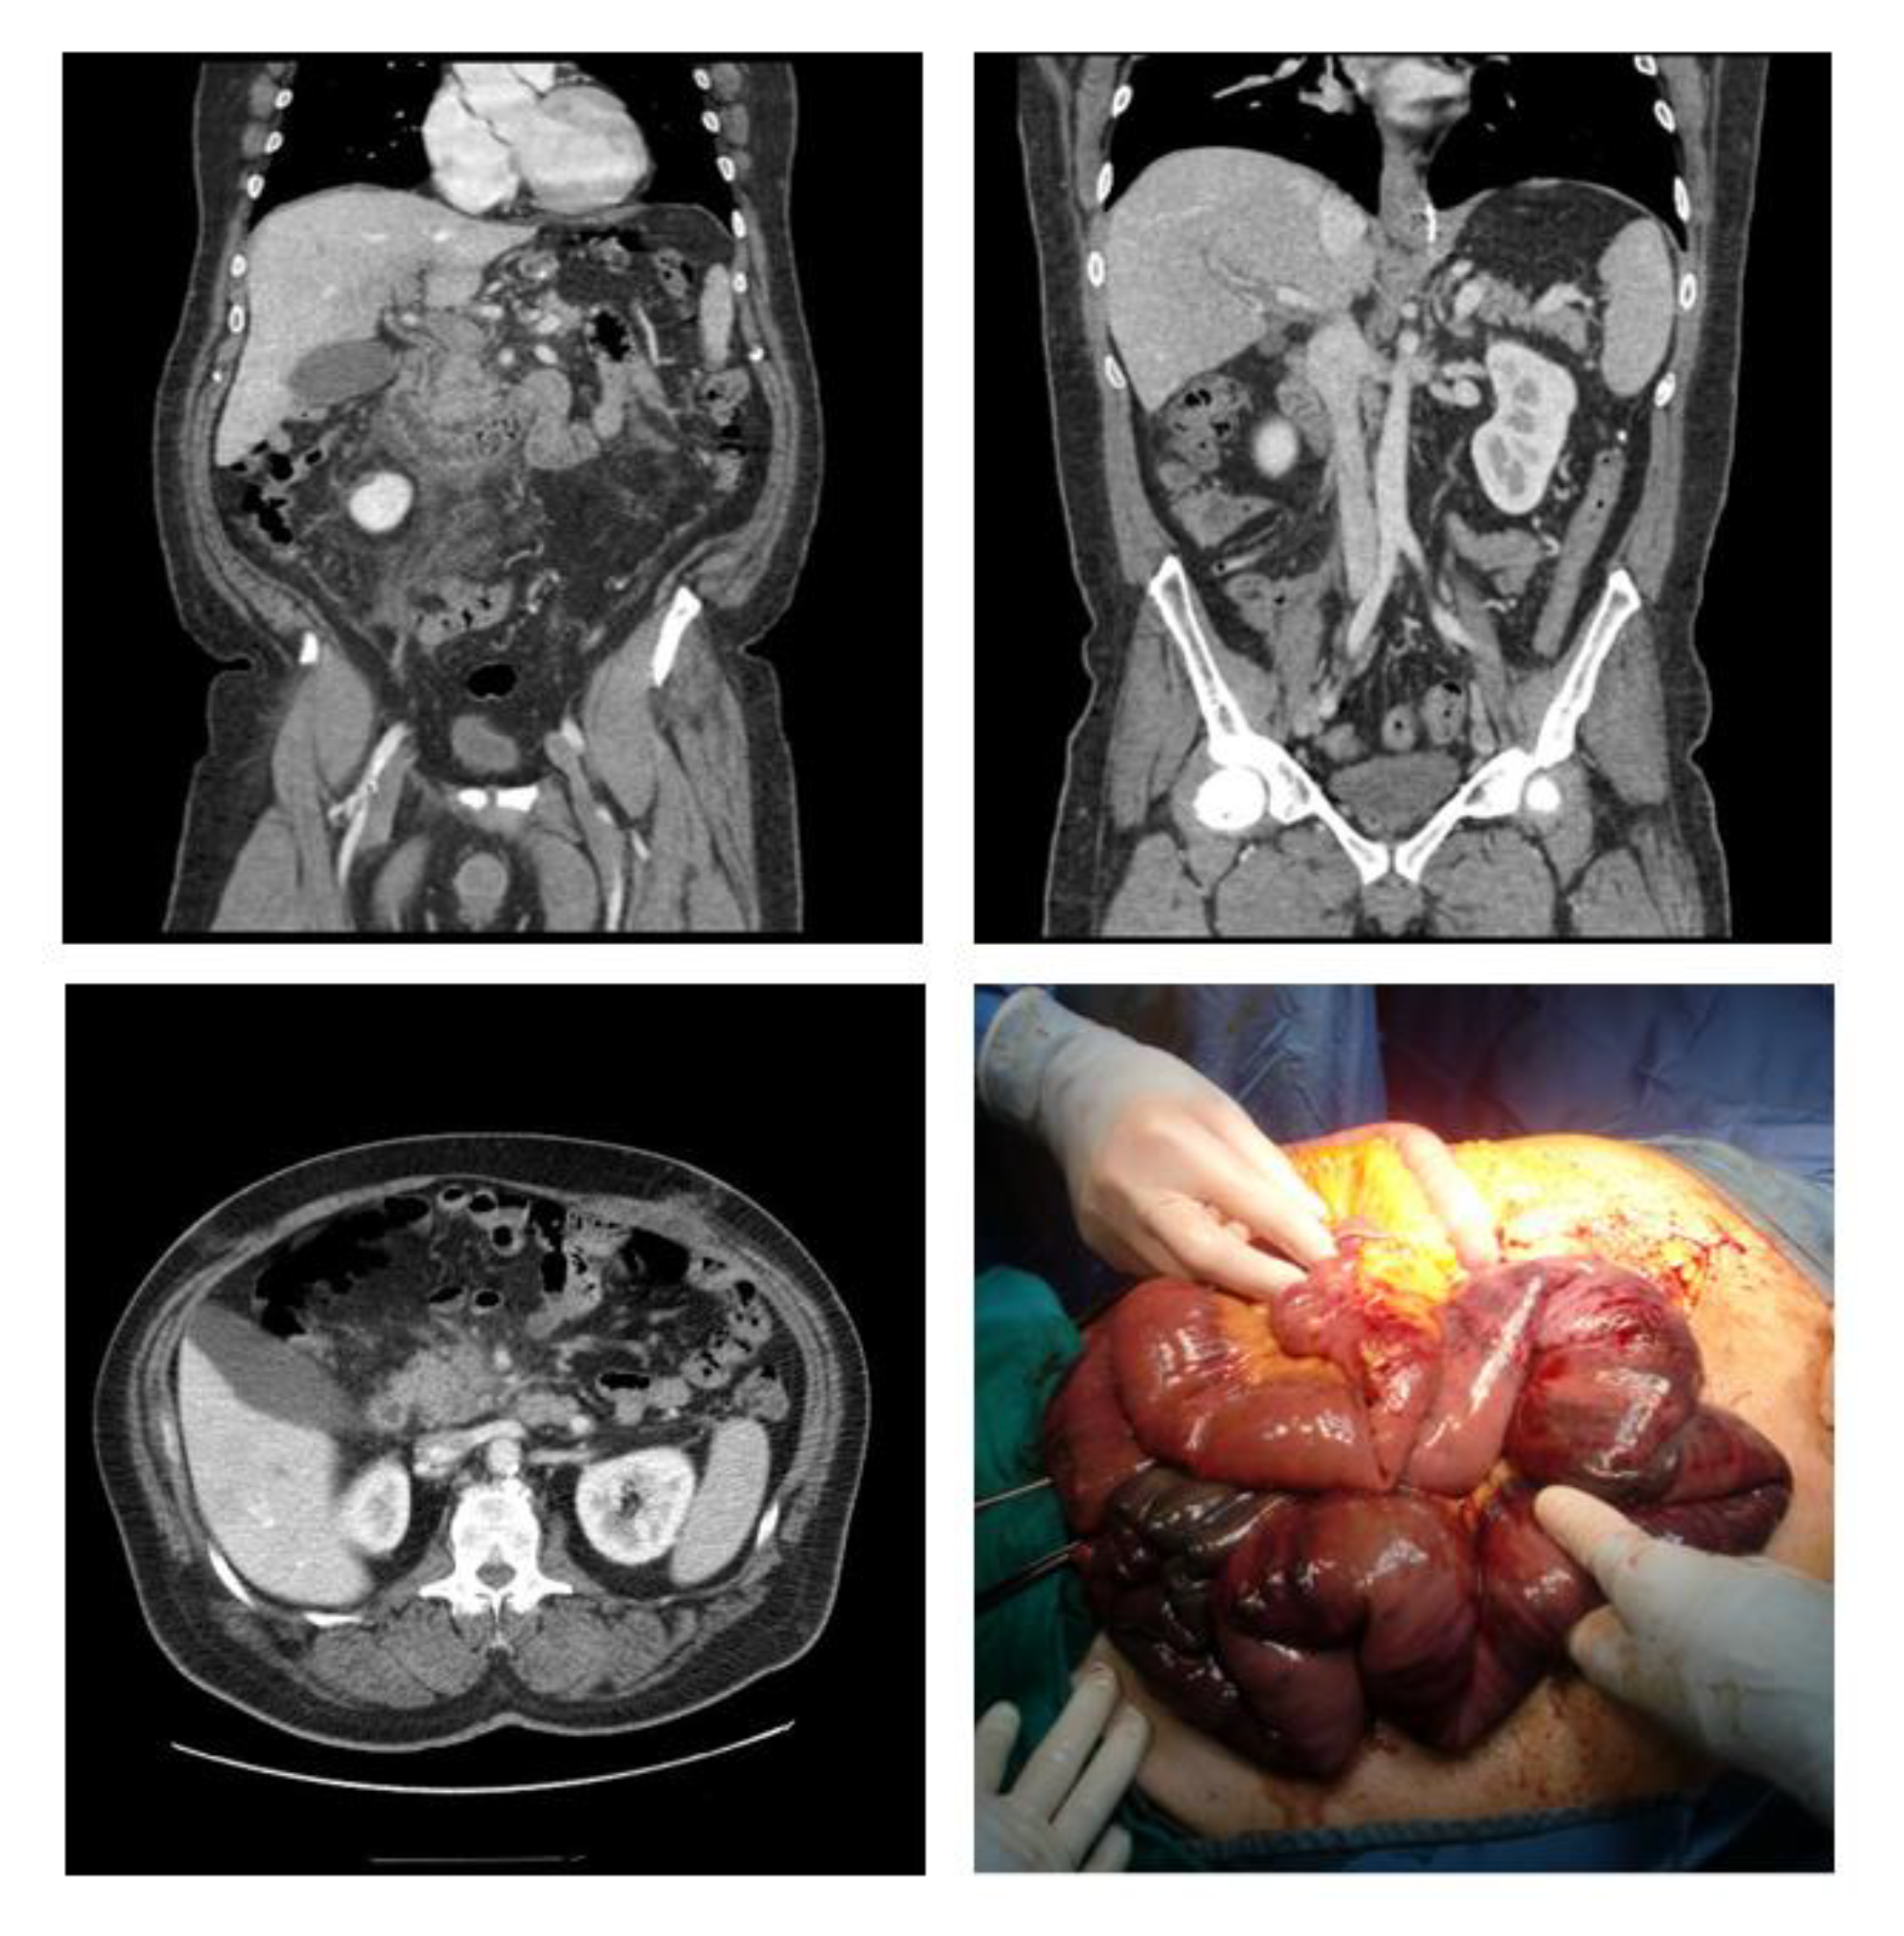

PMVT usually begins with a mild presentation that can be managed conservatively. However, in severe cases, it can potentially be lethal due to the risk of associated bowel ischemia (Figure 4) and potential late risk of chronic bilioportal cholangiopathy that can lead to small bowel resection and even liver transplantation [9]. Moreover, the occurrence of PMVT is among the factors that influence early postoperative liver function capacity of patients after bariatric surgery [10].

Figure 4.

Case of portal vein thrombosis after biliopancreatic diversion; CT scan showing extended PVT associated with bowel ischemia, and related intraoperative findings. PVT: Portal Vein Thrombosis.